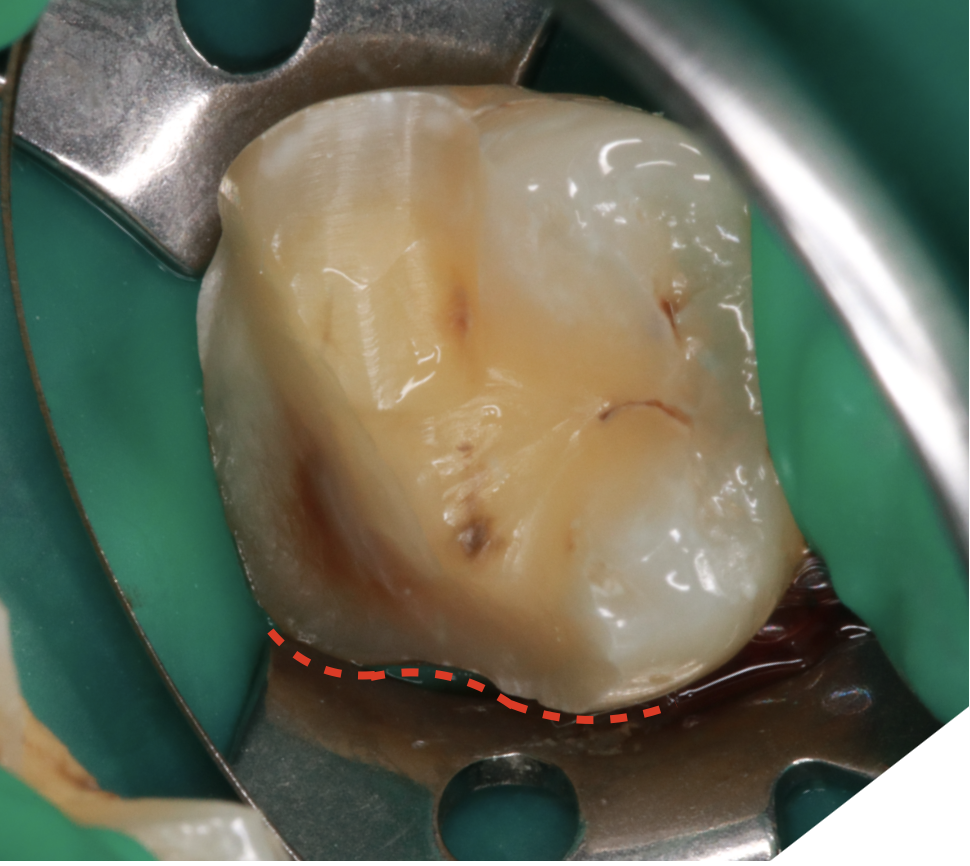

完善的隔離措施:

可以確保黏著過程中不被濕氣干擾

遠心的交界面幾乎沒入牙齦下

頰側觀: